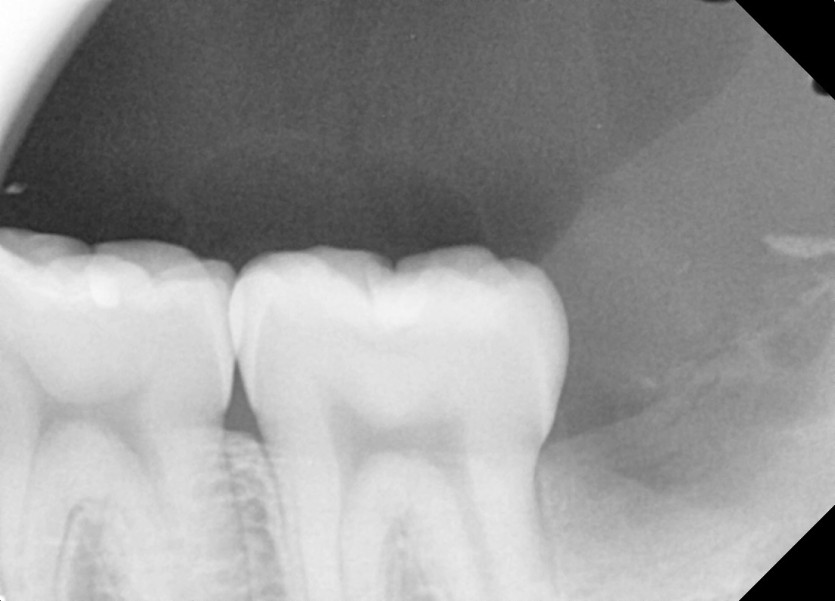

#28,38 사랑니 발치

구강 외과 전문의가 당일 발치하였습니다.